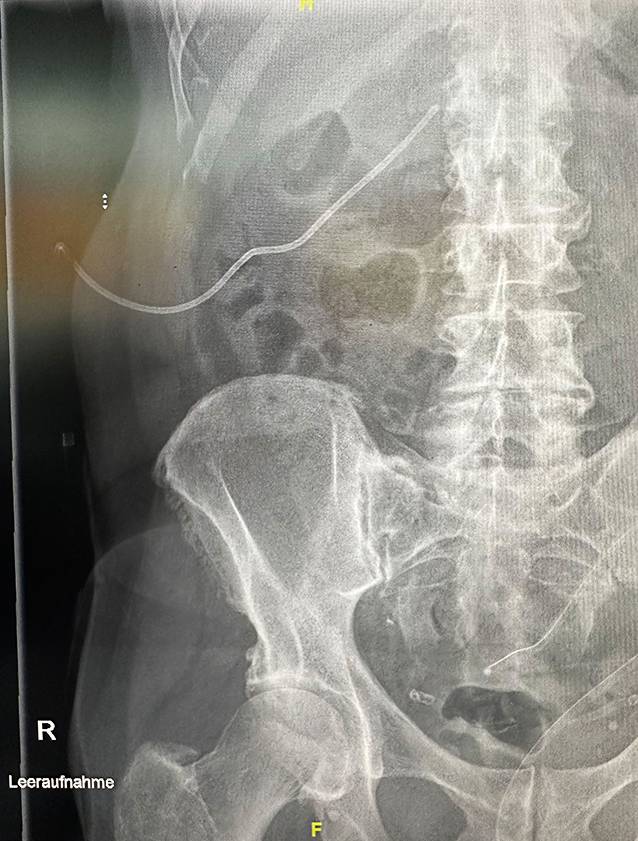

After 5 days, the patient presented on an emergency basis due to the clinical suspicion of a misplaced nephrostomy catheter. Biliary secretions were draining out of the catheter. There was no pain or fever or macrohematuria. Laboratory chemistry tests did not show any elevated infection parameters. On ultrasound, grade 2–3 hydronephrosis was found in the right renal pelvicalyceal system, and the left kidney was unobstructed. A plain X‑ray in one plane showed the nephrostomy from the right side with the tip projecting into the renal pelvis at the level of the right transverse process of L1 (Fig. 1).

Fig. 1

Nephrostomy catheter in place, plain X‑ray at the time of admission